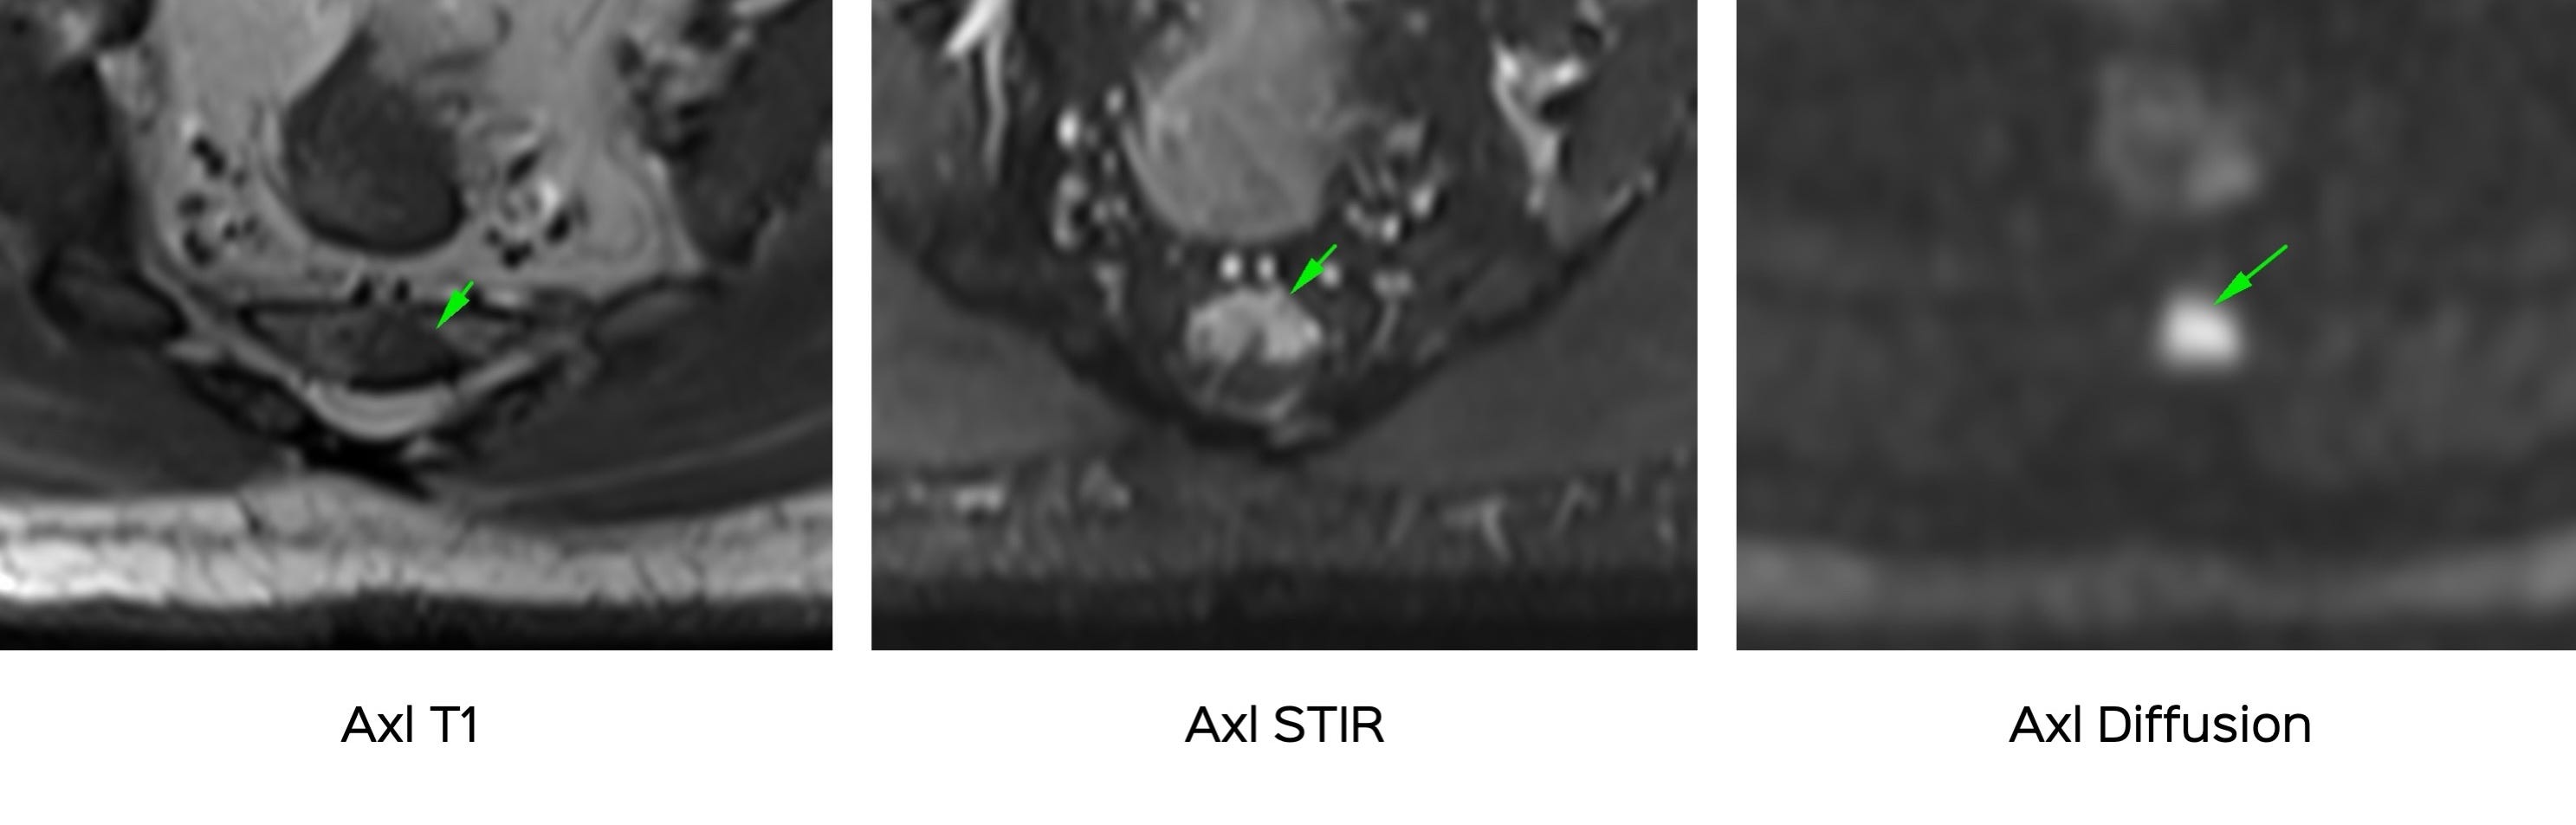

This 51-years old presented with erratic coccygeal pain. The MRI showed these findings.

The patient’s symptoms and MRI did not match. A PET/CT was then done for further work-up.